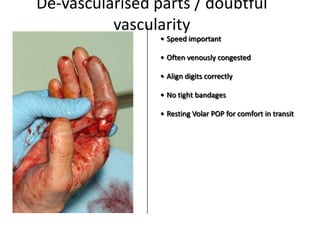

- Conditions that require emergency referral are discussed, such as bleeding, amputation, replantation, compartment syndrome, infections, and high pressure injection injuries. Proper management of these conditions focuses on rapid assessment and treatment to prevent further tissue damage.